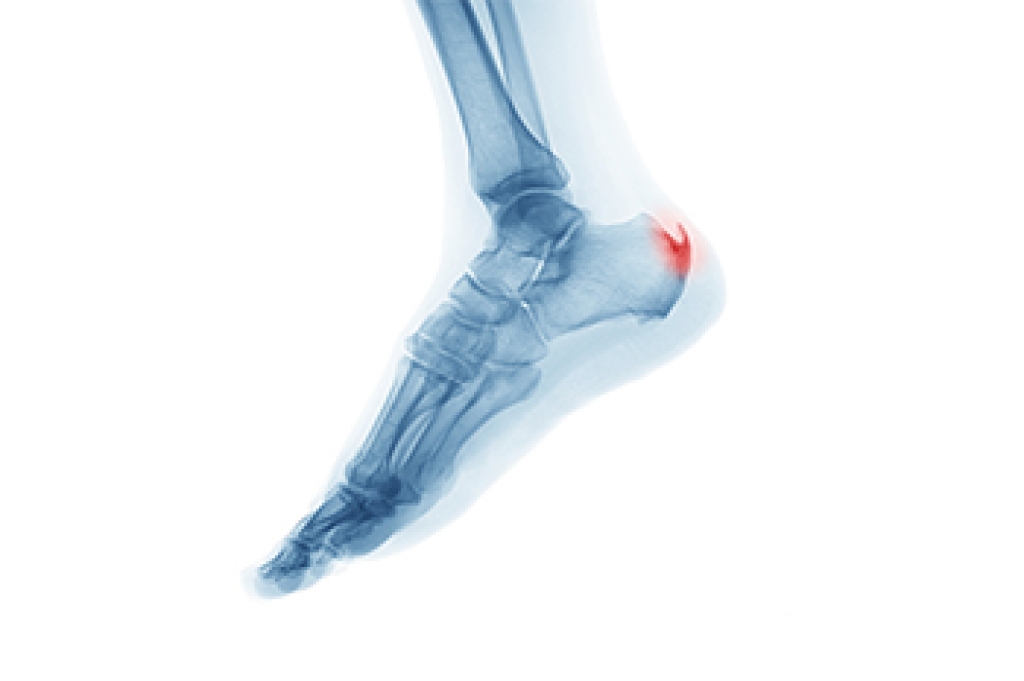

To figure out the cause of foot pain, podiatrists utilize several different methods. This can range from simple visual inspections and sensation tests to X-rays and MRI scans. Prior medical history, family medical history, and any recent physical traumatic events will all be taken into consideration for a proper diagnosis.